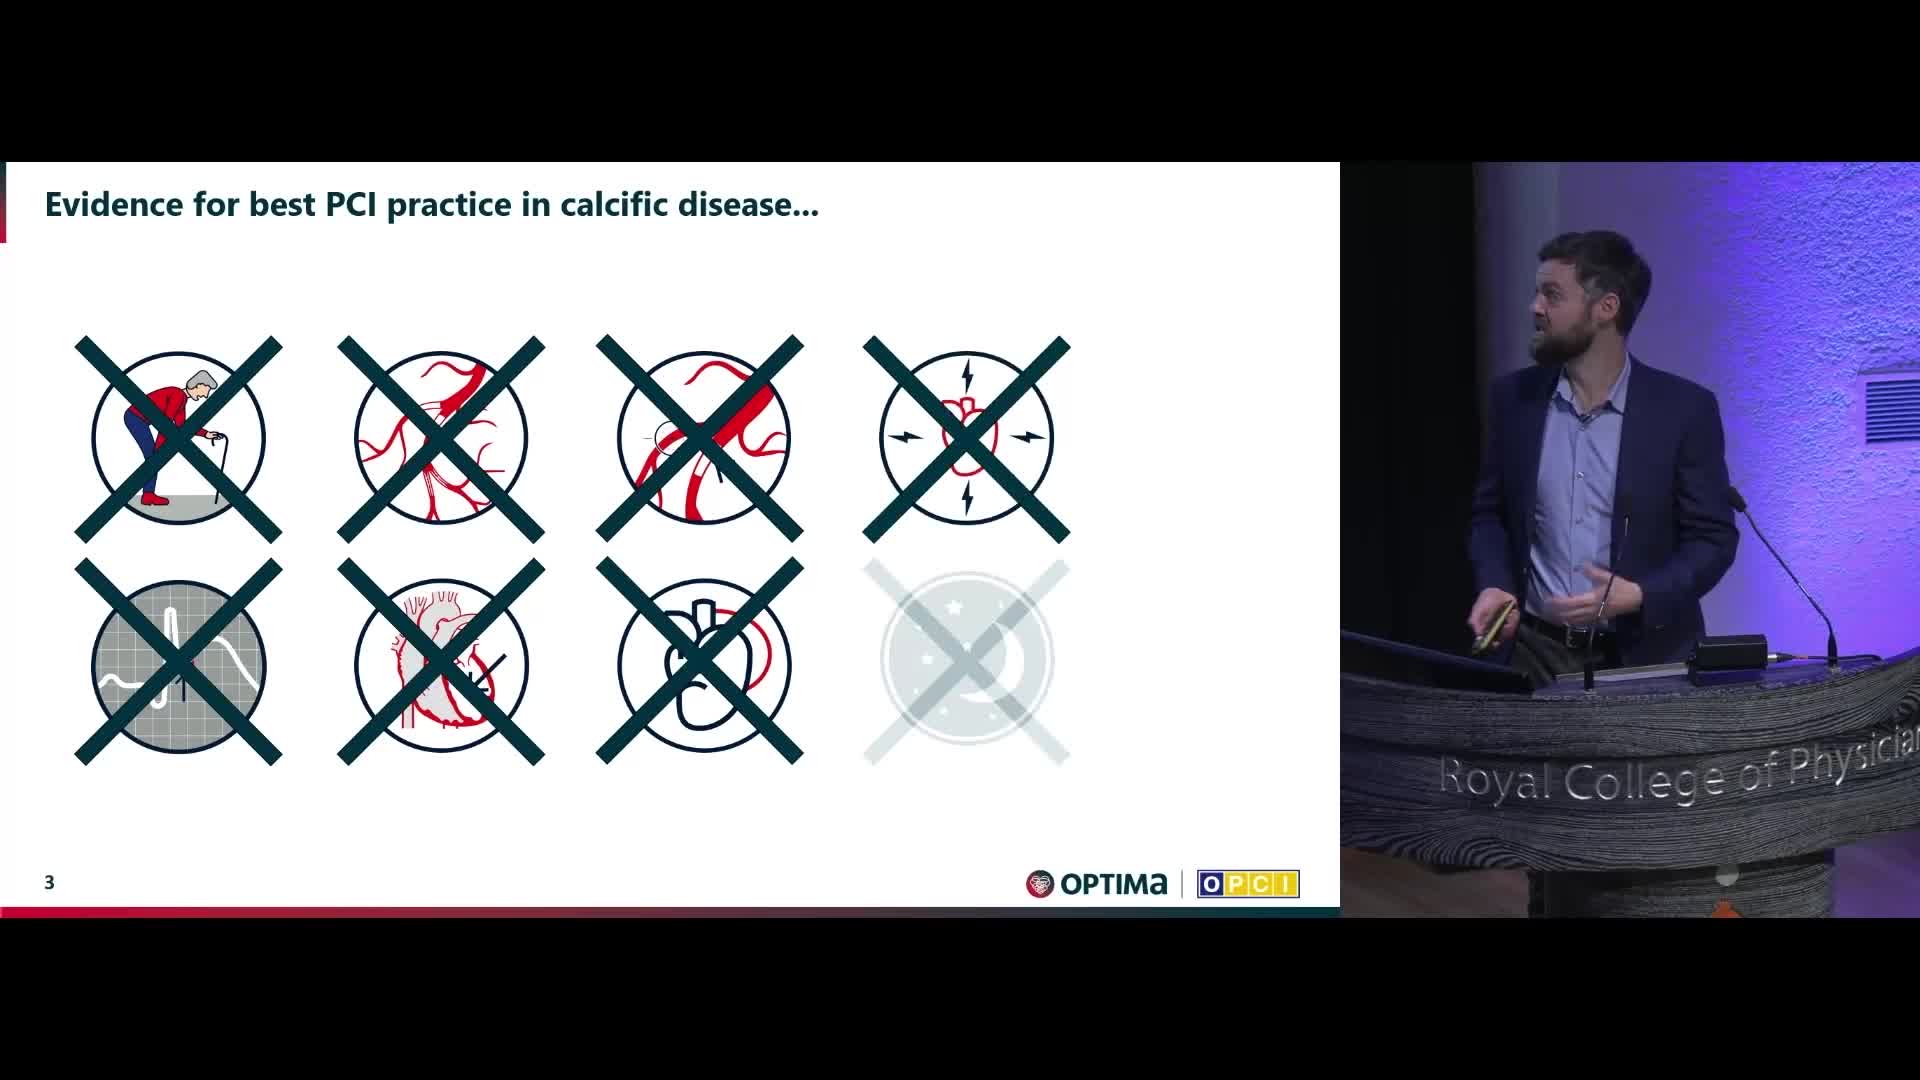

Session 2: Coronary calcium – too hard to crack?

Treatment of coronary arterial calcium (CAC) has being redefined. We explore the interaction between CAC and patient...